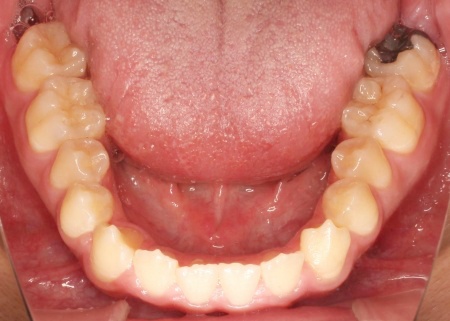

まず、下奥歯(臼歯)を歯茎の外側に持ち上げる「挺出(ていしゅつ)」という処置を行いました。

奥歯が少し高くなることで、下顎全体がわずかに後ろへ動くため、前歯の噛み合わせが整いやすくなります。

加えて、上下の前歯には「IPR」という処置を行いました。これは、歯の表面のエナメル質をごくわずかに削り、歯を動かすためのスペースを作る方法です。

このスペースを利用して前歯を後方へ移動させ、審美性の改善を目指しました。